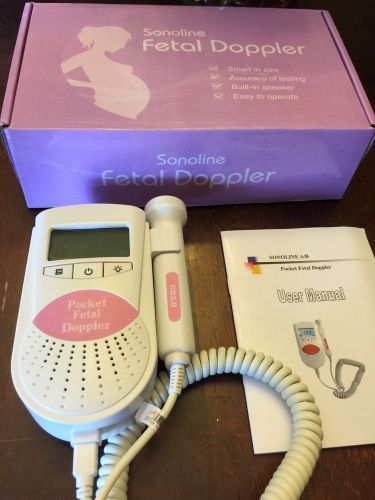

Sonoline B fetal Doppler, Baby Heart Monitor, 3Mhz probe, batteries, FDA